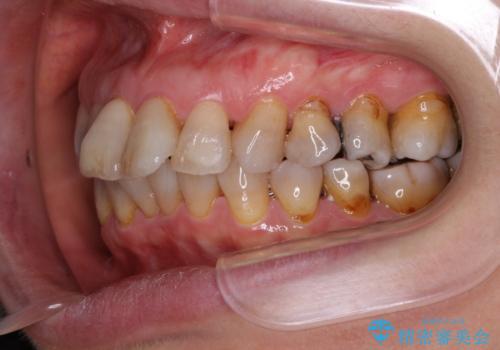

- 突出した口元を引っ込めることを希望して来院された患者様です。

上下左右第一小臼歯4本を抜歯して、口元を改善するワイヤー矯正を行うこととしました。

長年気にされていた口元の突出感が改善されたため、もっと若い時分に矯正をすればよかったと思われていました。